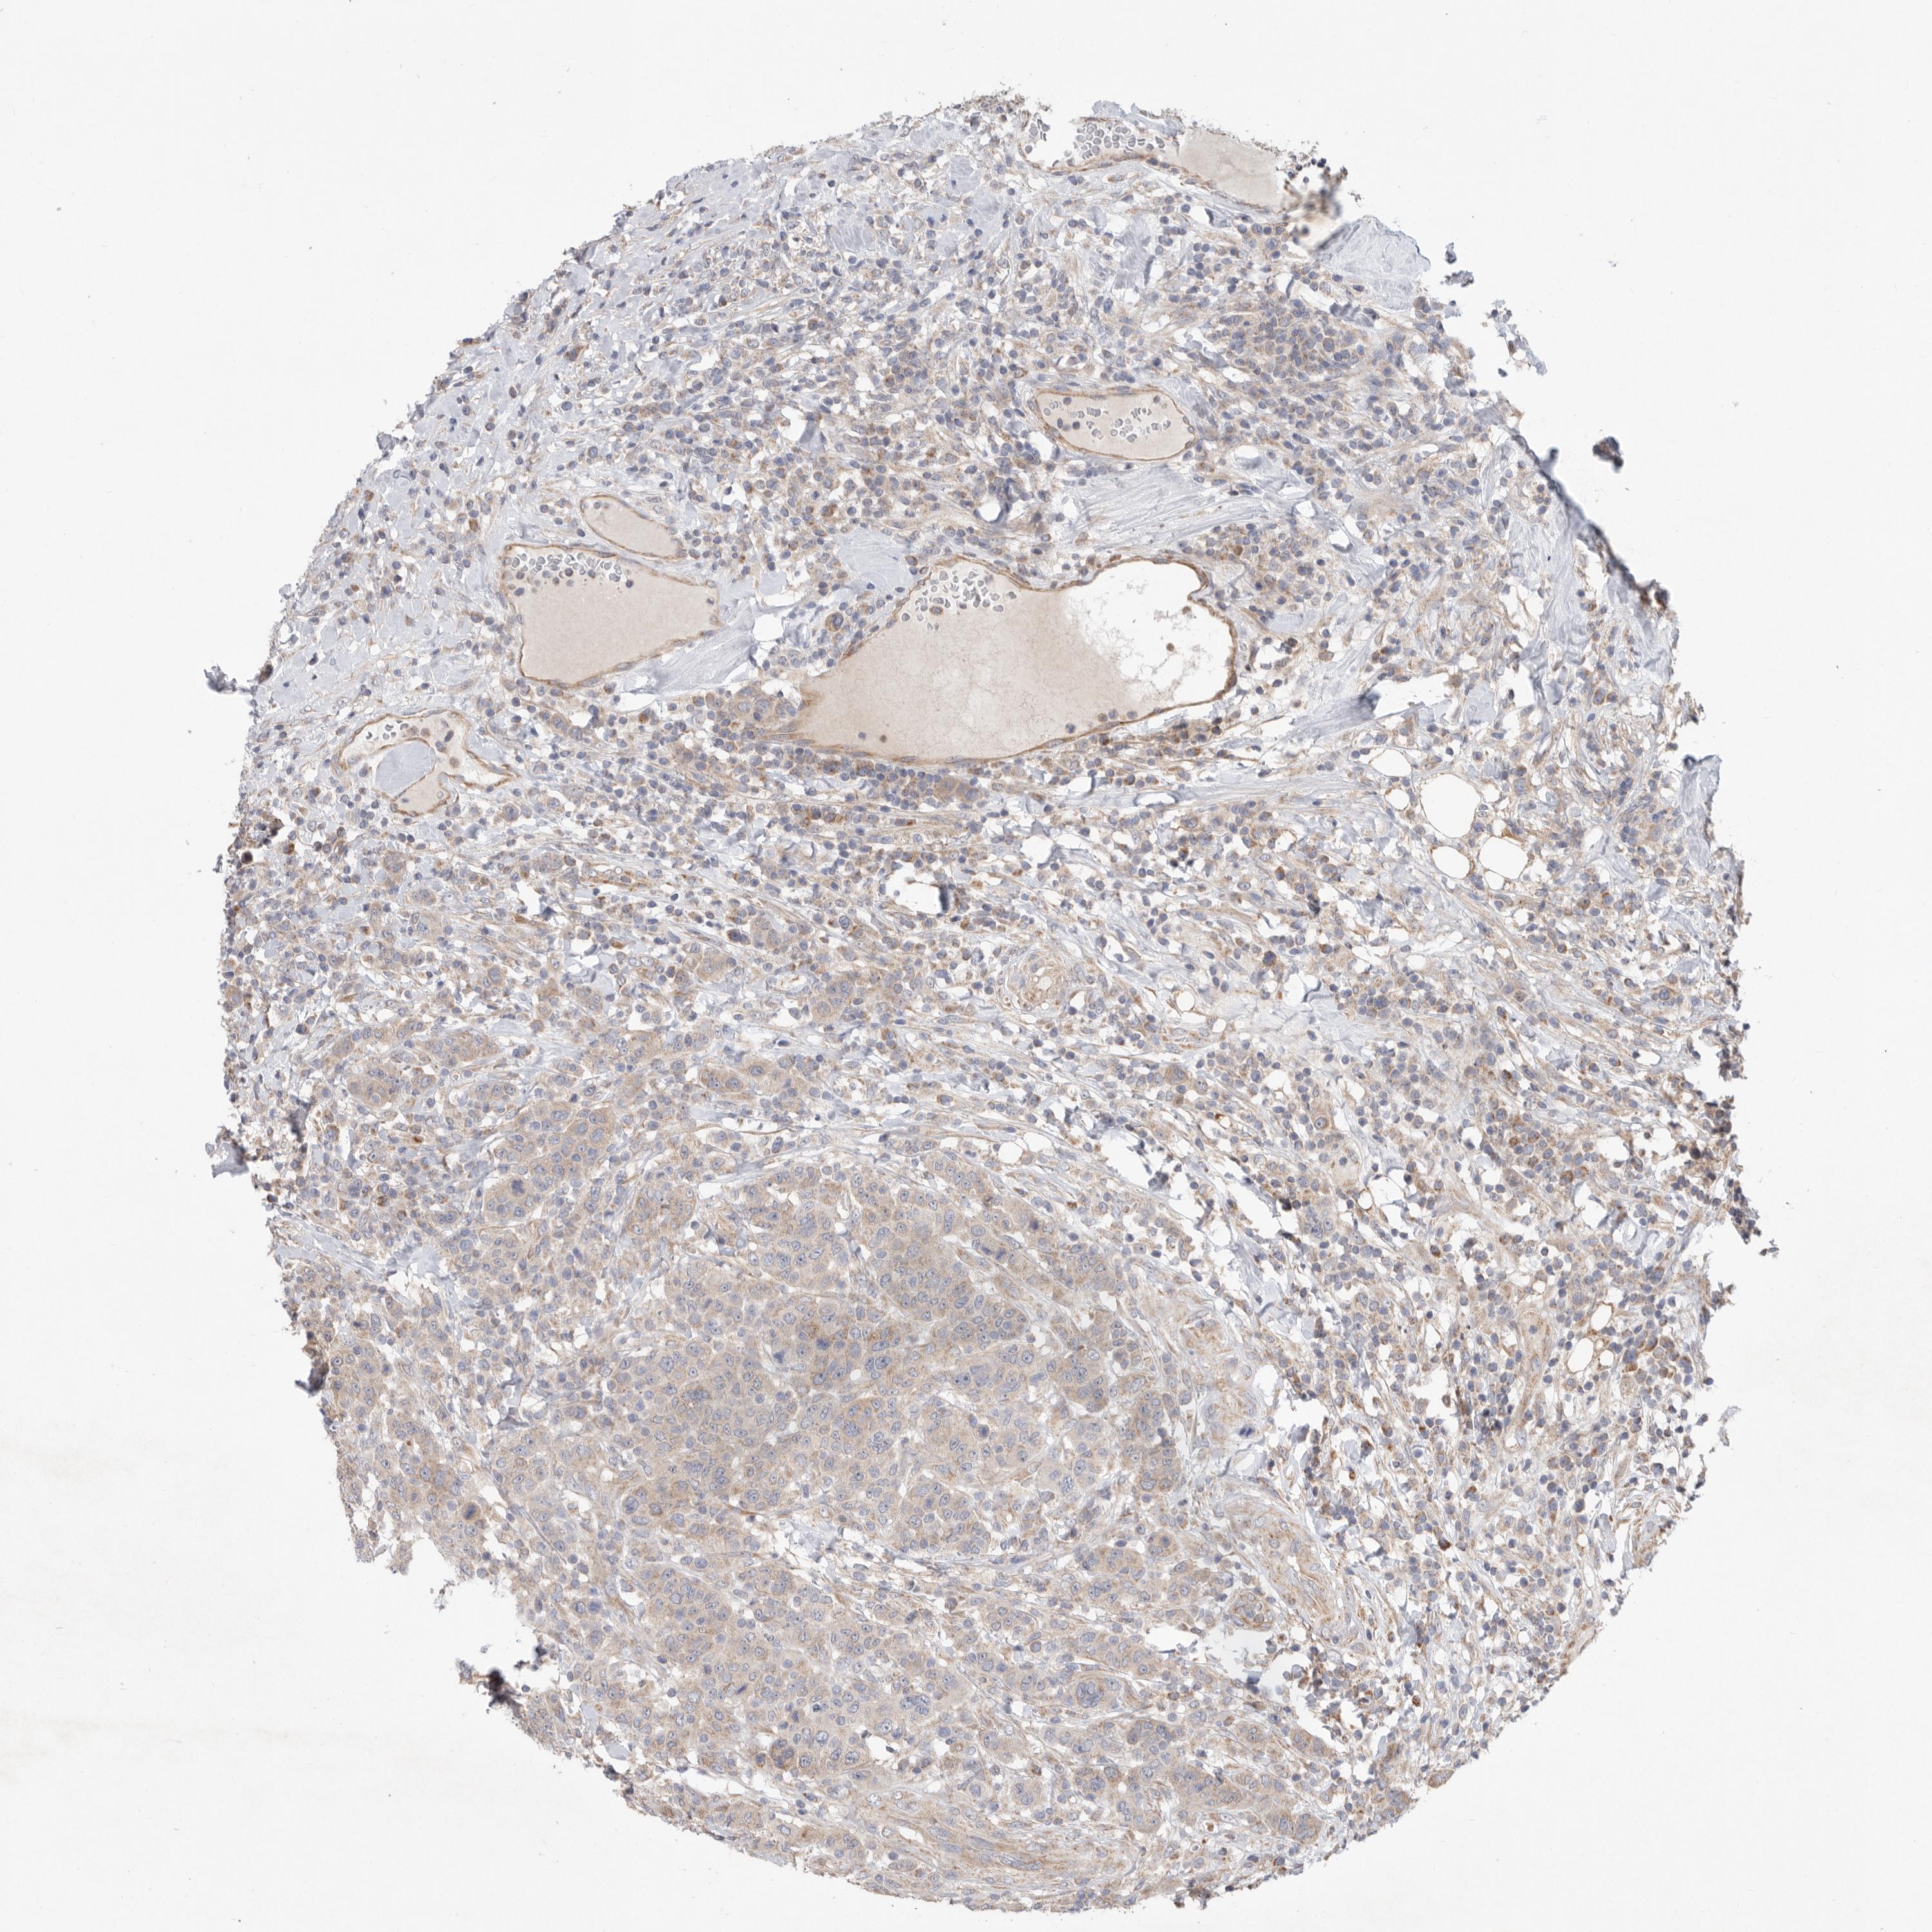

BRCA TCGA BRCA VALIDATION PROTEIN EXPRESSION

Breast cancer

Human cancer